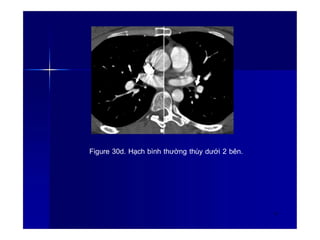

Figure 30a. Hạch bình thường vùng rốn phổi 2

bên.

40

Figure 30d. Hạch bình thường thùy dưới 2 bên.

43